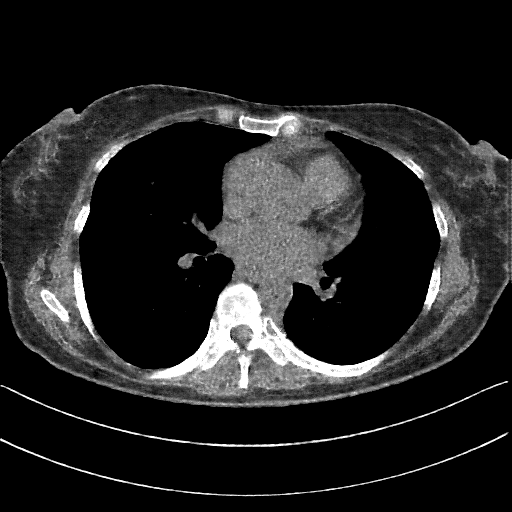

Generated VENOUS CT scan (A→B translation)

Full window (WL 1023.5, WW 4095 β†’ Low βˆ’1024, High +3071)

Actual HU range: [-1024.0, 1512.9]

Lung window (WL -600, WW 1500 β†’ Low βˆ’1350, High +150)

Actual HU range: [-1241.2, 150.0]

Mediastinum window (WL 40, WW 400 β†’ Low βˆ’160, High +240)

Actual HU range: [-160.0, 240.0]